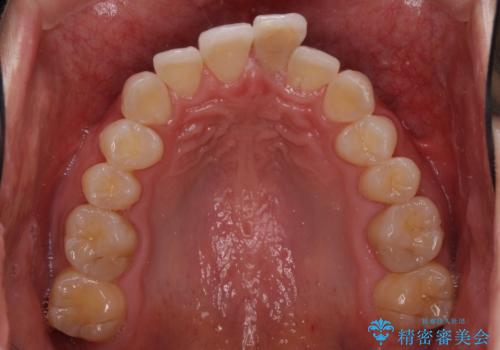

- 前歯のデコボコを治したいとのことで来院された患者様です。

上下顎ともに歯列全体の後方移動とIPR(歯と歯の間を削る)によってデコボコが解消するように設計し、インビザラインにより治療を行うこととしました。